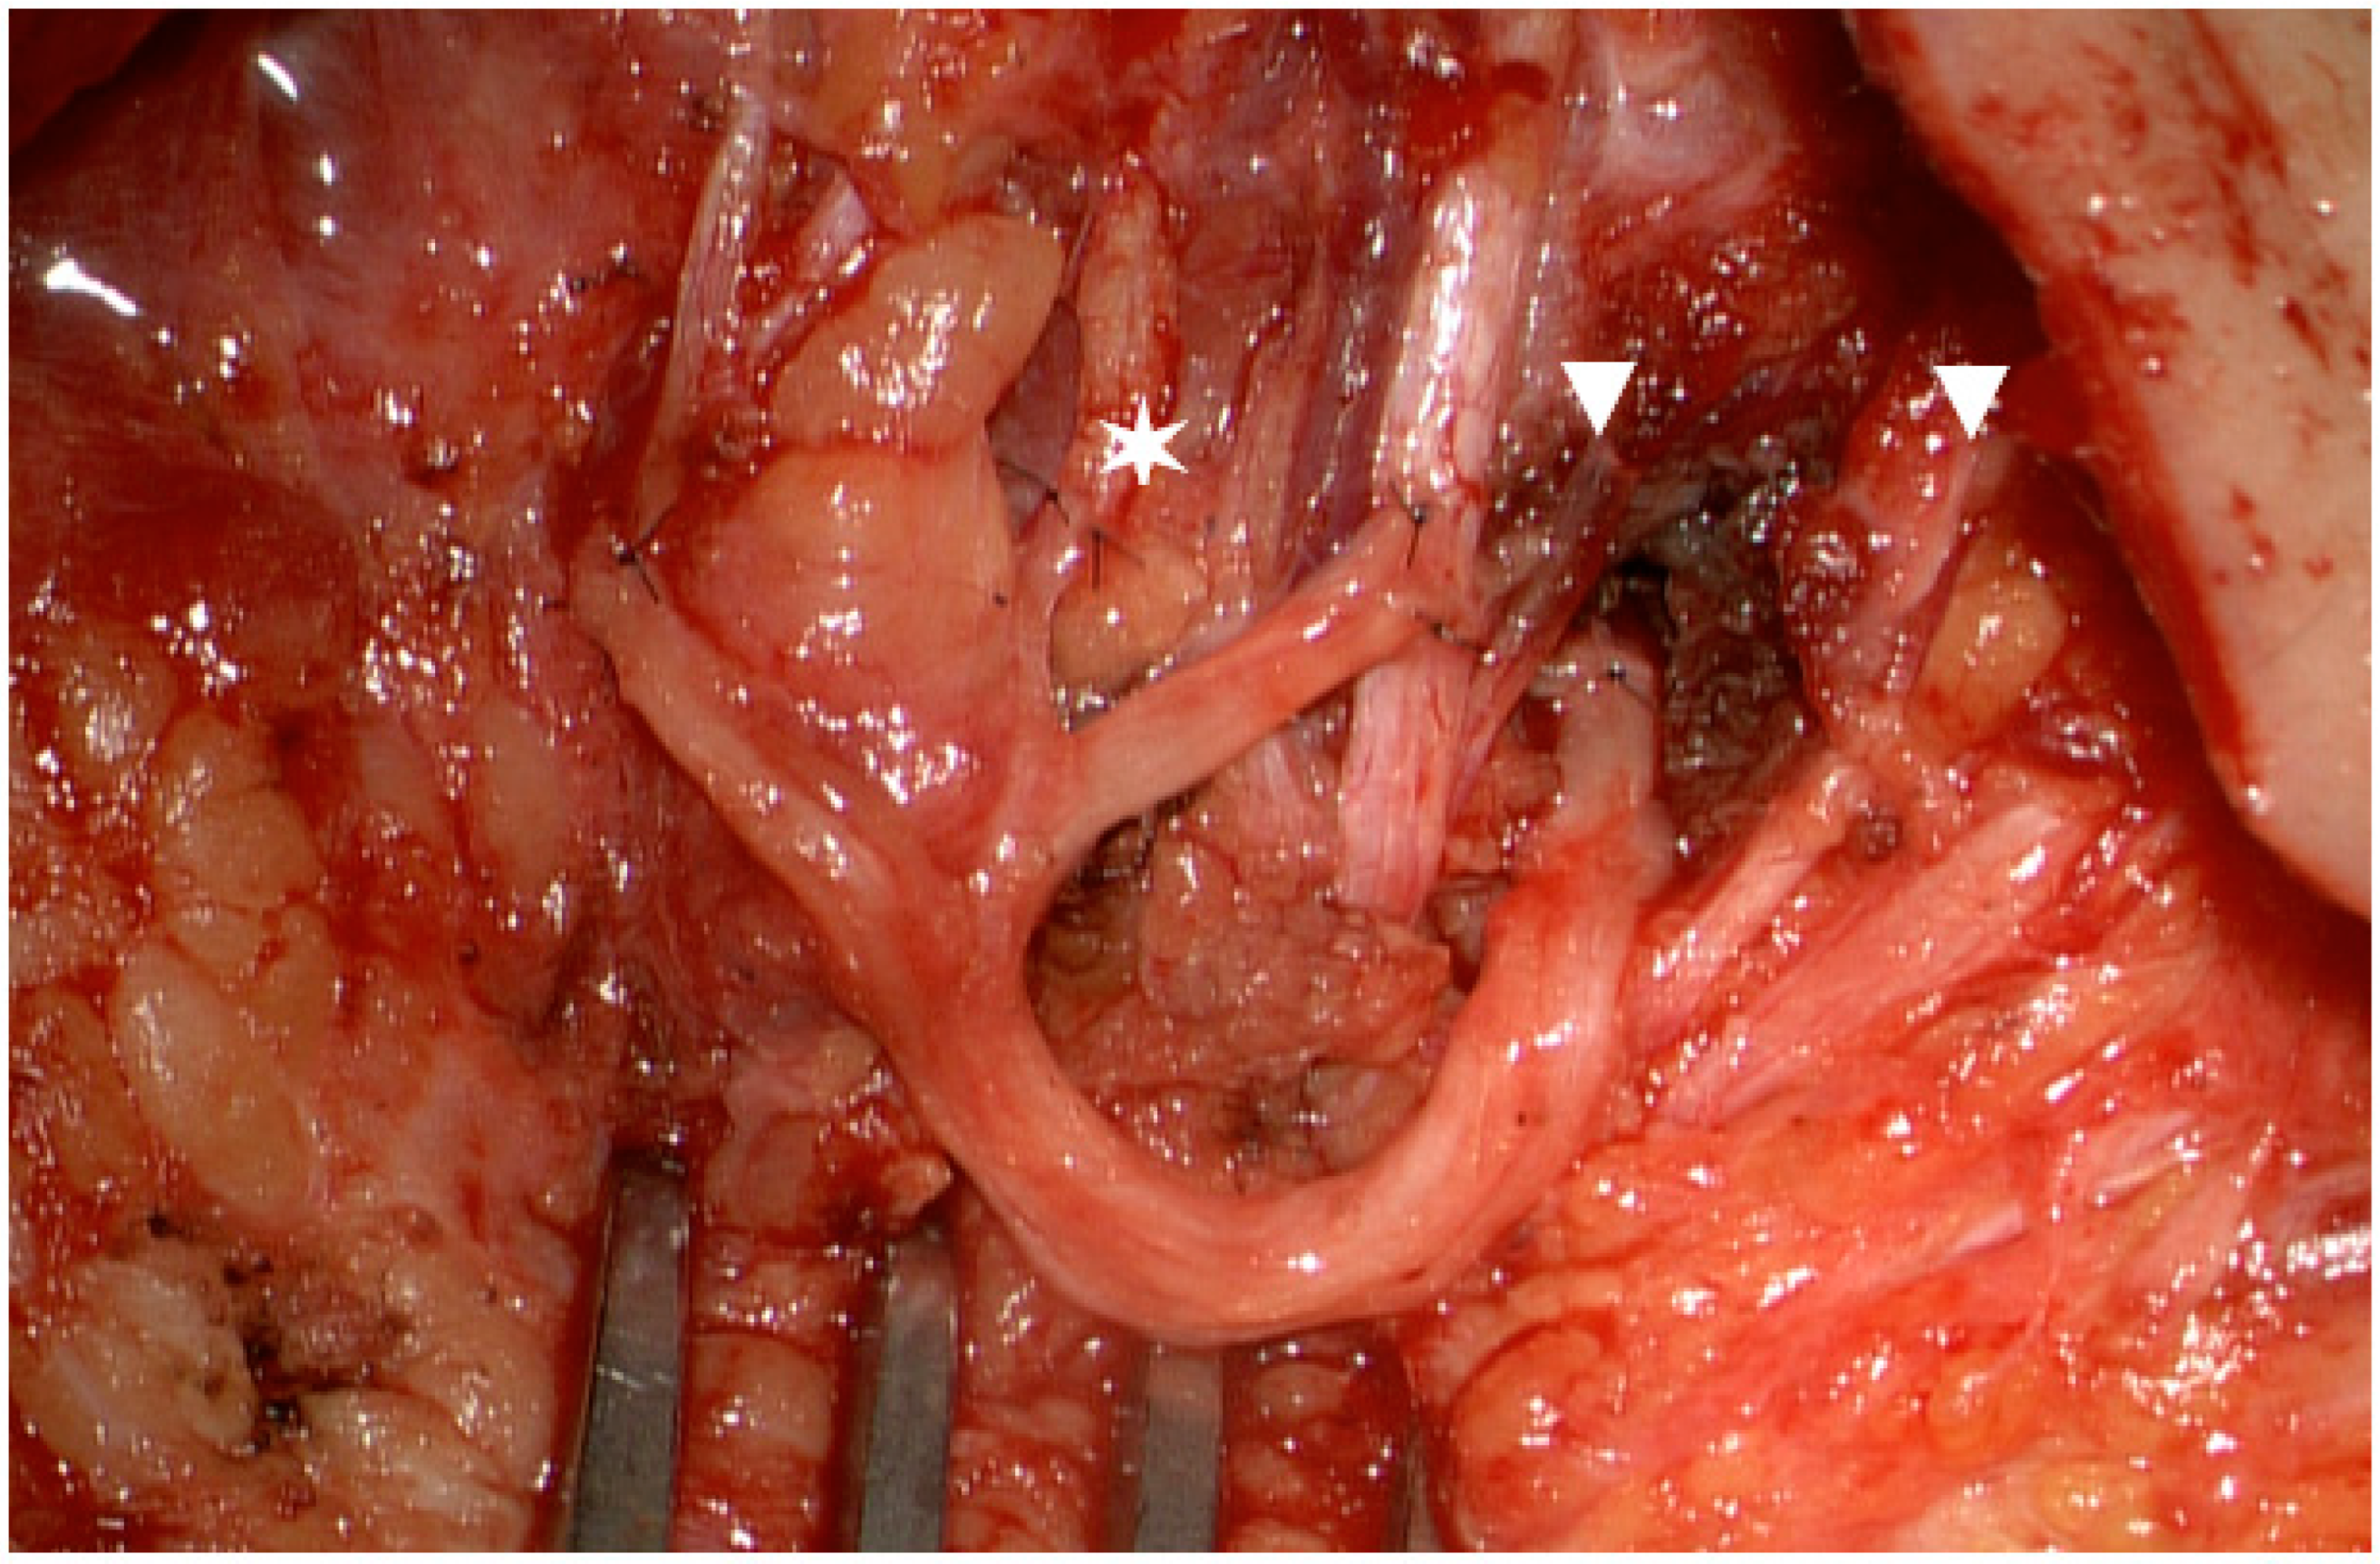

3.2. Advances of Nerve Bridging and Transfer